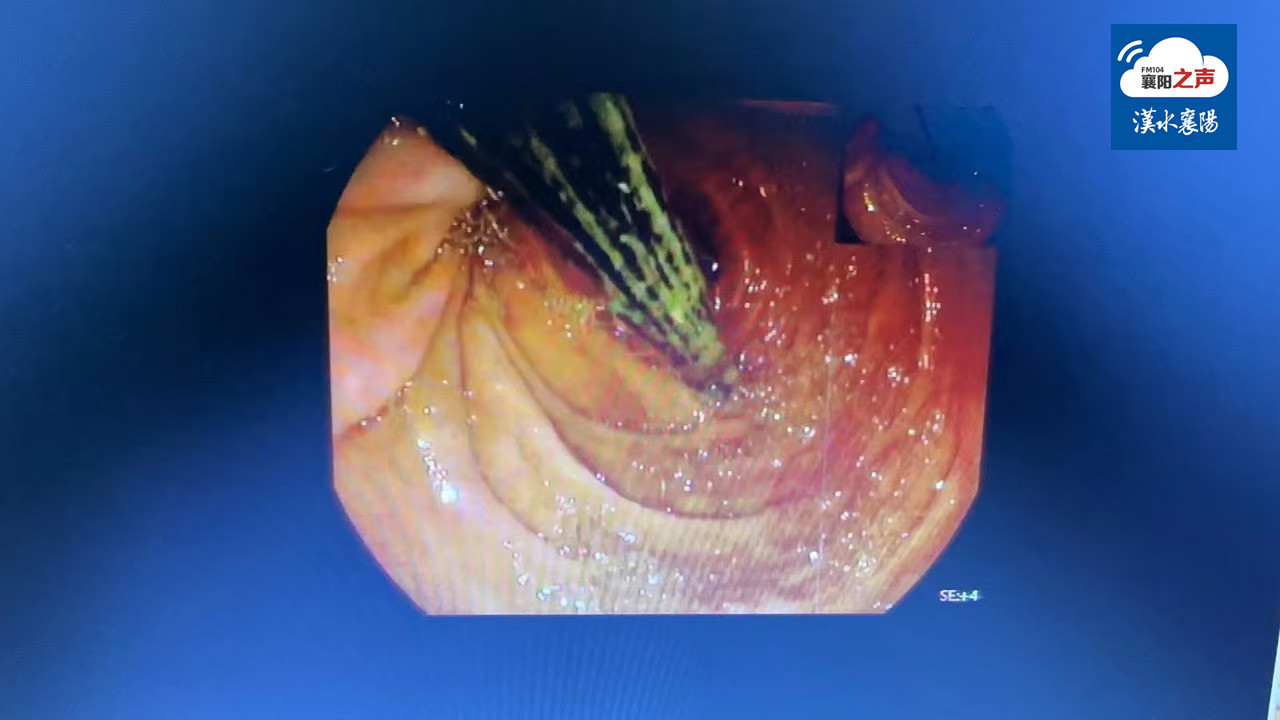

经过充分的评估,医疗团队决定,在全麻插管下,对李先生行急诊胃镜探查。当胃镜进入十二指肠,见筷子形态质地正常,一端嵌顿于球部前壁,一端嵌顿于降部乳头对侧,呈纵轴嵌顿于十二指肠球部至降部之间,嵌顿处可见深溃疡形成。

医生首先利用异物钳松动筷子嵌顿部,然后利用角度挑出嵌顿筷子端,同法挑出筷子另一端,然后通过异物钳结合圈套器成功将筷子以平行于食管腔的方向取到口腔。筷子到口腔后,因口腔下咽与食管有近70度夹角,反复调整方向无法取出。危急关头,由消化内镜中心经验丰富的护士用口垫撑开口腔,让内镜退出,用圈套器套紧筷子后顺着舌根角度缓慢拉取,最终将困扰李先生多年的这支筷子顺利取出。

经测量,取出的筷子长度约16cm。再次进镜观察,见十二指肠筷子嵌顿处有深凹溃疡形成,在内镜直视下置入鼻空肠营养管至十二指肠水平部以下,并置入胃管行胃肠减压。术后,患者返回病房,无腹痛、腹胀等症状发生。